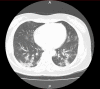

Coronavirus disease 2019 (COVID-19) is a respiratory tract infection caused by SARS-CoV-2. As of March 30, 2020, there have been 693,224 reported patients with COVID-19 worldwide, with 1,446 in Japan. Currently, although aspects of the route of transmission are unclear, infection by contact and by inhaling droplets is considered to be the dominant transmission route. Inflammatory symptoms in the upper respiratory tract persist for several days to 1 week after onset, and in some patients symptoms of pneumonia worsen and become severe. The presence of underlying diseases and advanced age are risk factors for increased severity. Diagnosis is based on detection of SARS-CoV-2 by polymerase chain reaction (PCR) testing of nasopharyngeal swabs or sputum. Symptomatic management is the main treatment for this disease. Although the efficacy of several agents is currently being tested, at present there is no effective therapeutic agent. To prevent infection, in addition to standard preventive measures, measures that counteract infection by contact and droplet inhalation are important. In addition, if procedures that cause aerosolization of virus are used, then measures that prevent airborne infection should be implemented.